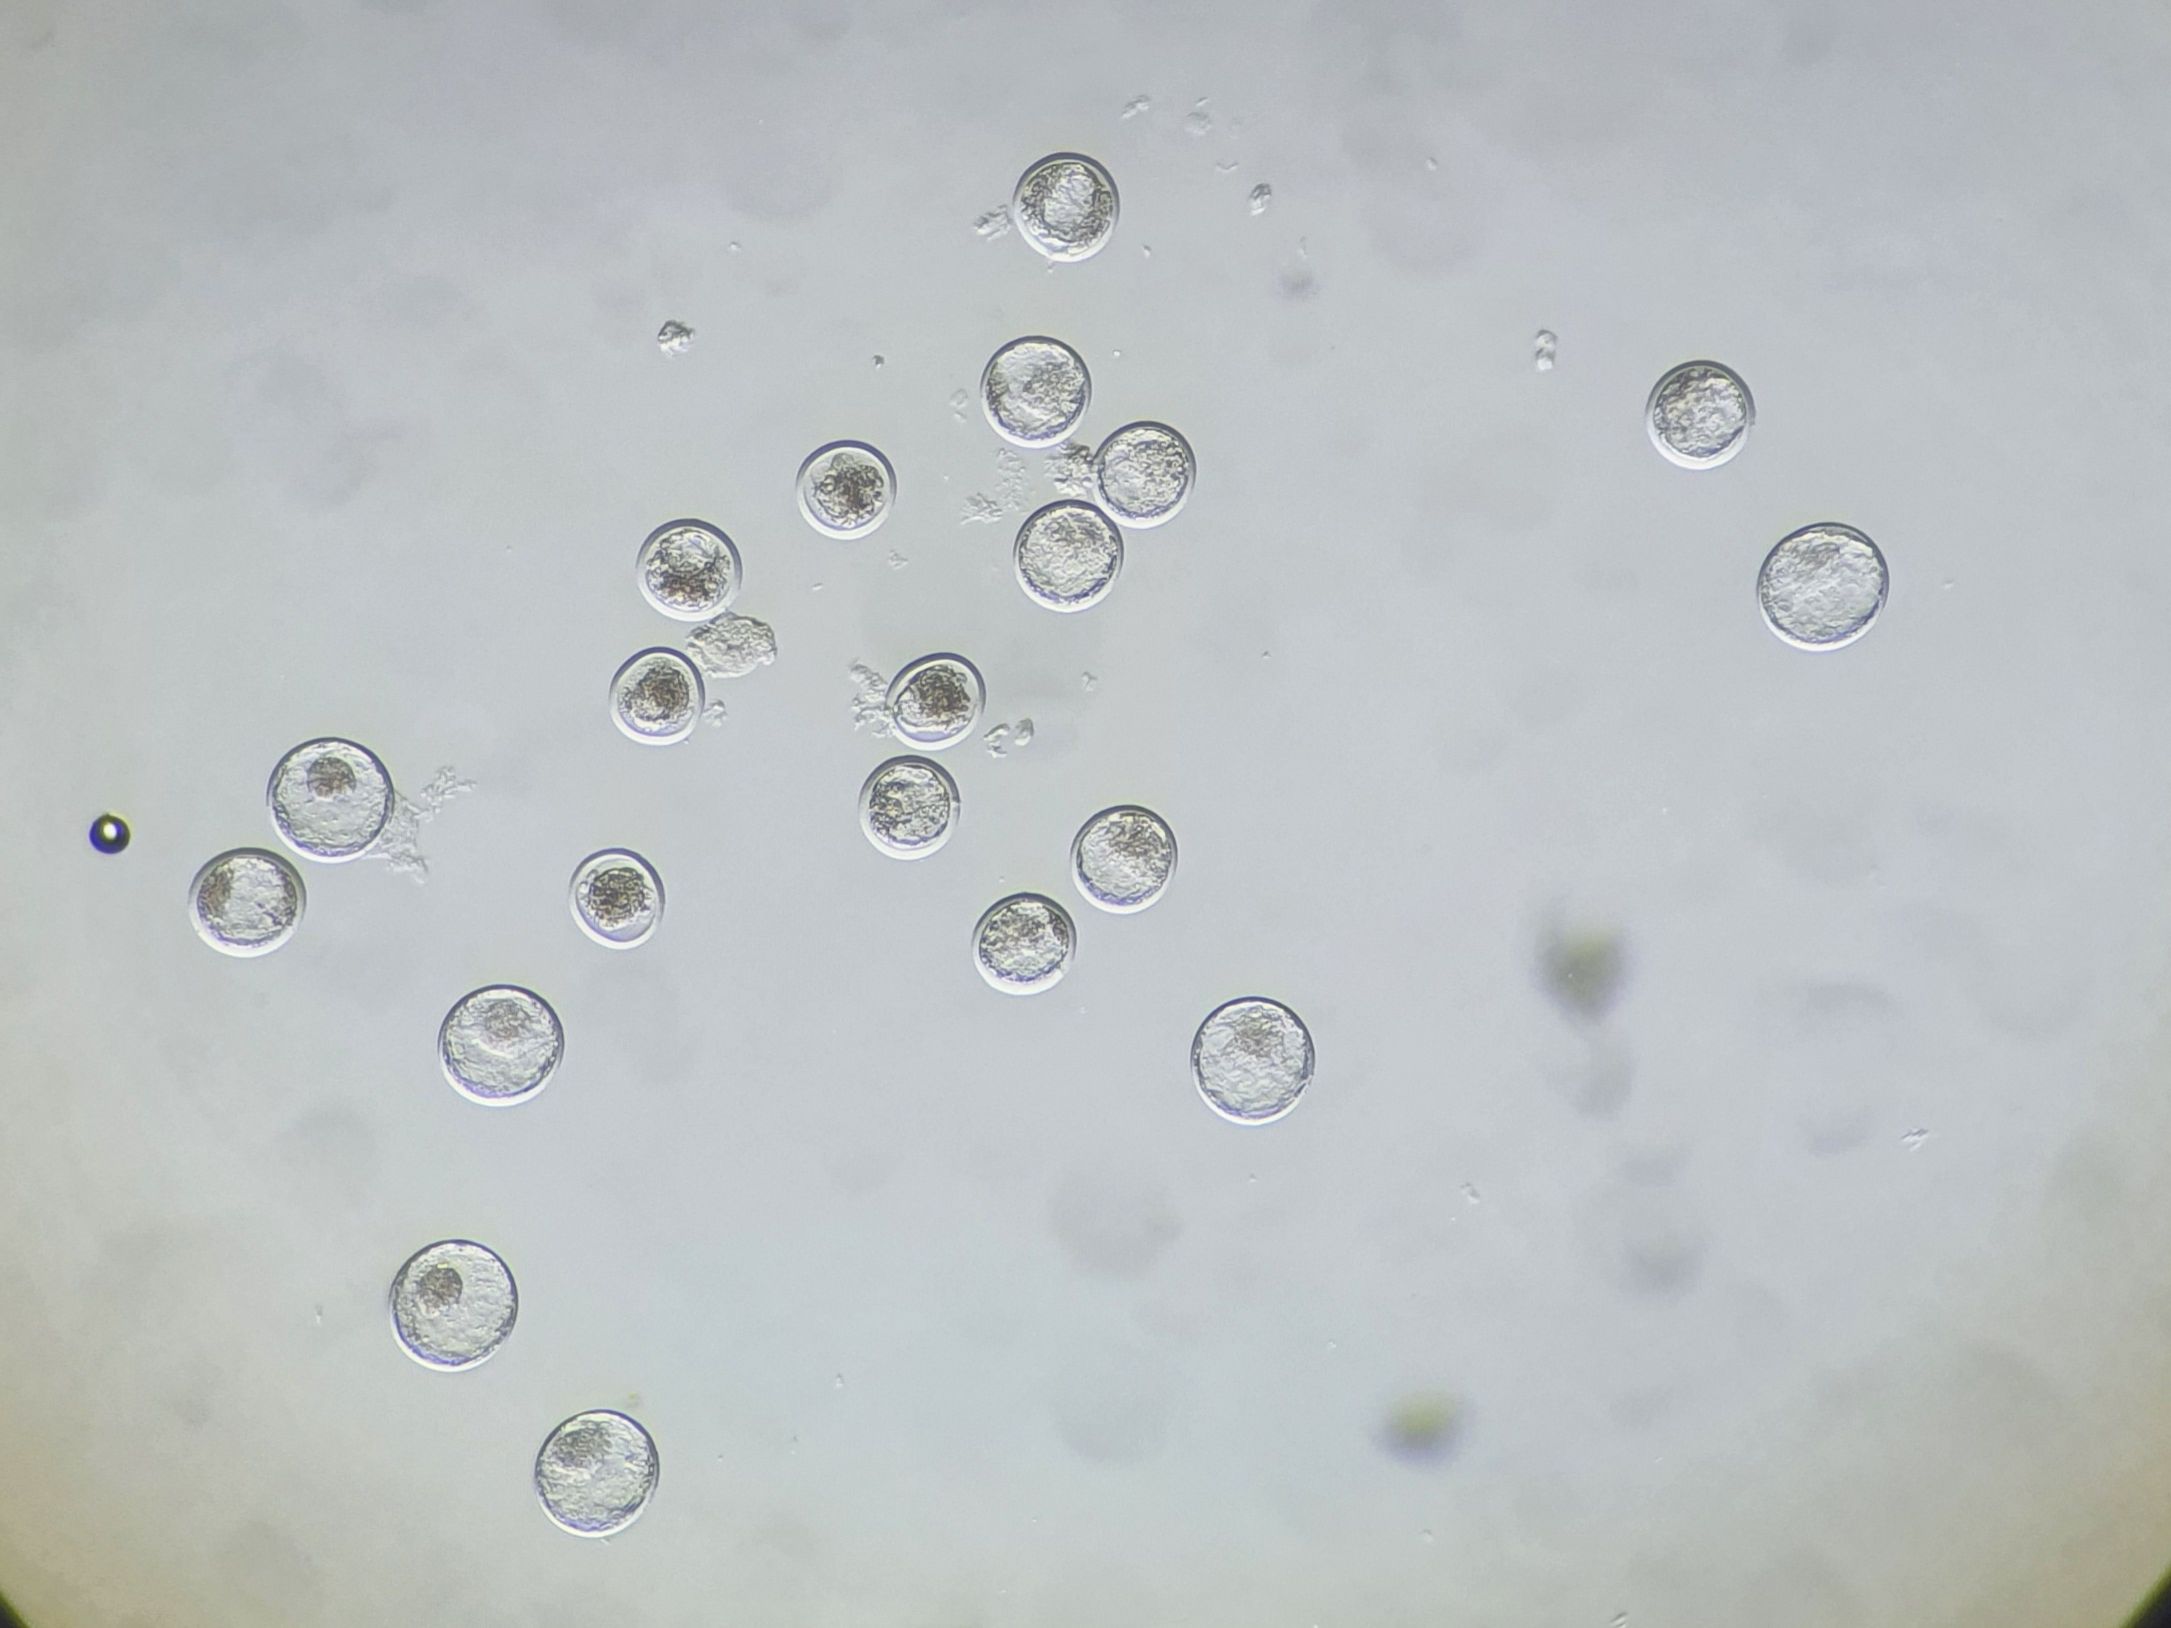

Danach wird die Spüllösung gefiltert und es wird mit dem Mikroskop nach den Embryonen gesucht.

-

Dabei ist die Feststellung des Entwicklungsstadiums (1-9) und die Qualitätsbeurteilung (1-4) des Embryos von Bedeutung.

Die Einteilung ist international gültig.